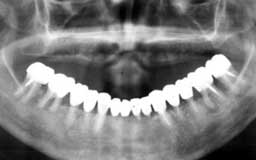

Eさん 初診時 53歳 女性

残存歯数26本とはいえ、10代のころみたいな万全な状態の歯は1本もなく、クラウンの中は 虫歯、歯周疾患も末期の状態です。徹底的な治療とメインテナンスが必要と思われます

Eさん 12年後 65歳

治療やメインテナンスに対する理解が得られず、主訴のみの治療で来院が途絶えてしまいまし た。その後他院を転々と受診したそうですが、約10年間に予想通り大半の歯を喪失

Eさん 17年後 70歳

再来院後は毎月のメインテナンスを継続され、今のところ何とか残存歯がそのまま機能してい ます